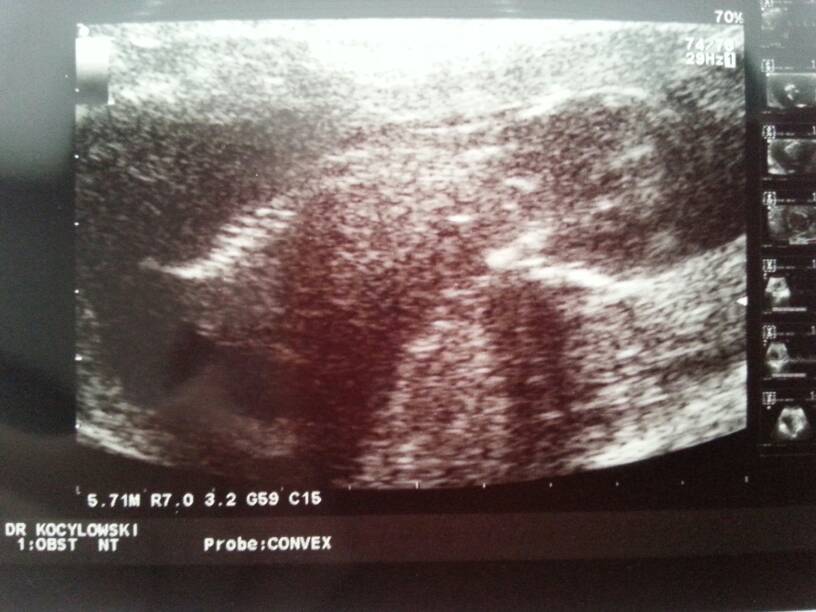

No i po :) obsuwa u lekarza = dobre wieści :) Maluch skakał całe badanie ale wszystko udało się pomierzyć, przezierność karkowa 1,9 na początku się przeraziłam ale takim CRL norma jest od 1,7 do 2,7 mm a CRL czyli długość 8.2 cm :) przepływy dobre, serce, żołądek, nerki, wątroba, mózg ok.kość nosowa jest a wynik testu papa za tydzień do odbioru.

Zdjęcie raczej pleców ale tylko takie dal więcej mam nagrane na płycie.